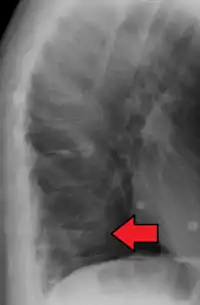

A compression fracture is a collapse of a vertebra. It may be due to trauma or due to a weakening of the vertebra (compare with burst fracture). This weakening is seen in patients with osteoporosis or osteogenesis imperfecta, lytic lesions from metastatic or primary tumors,[1] or infection.[2] In healthy patients, it is most often seen in individuals suffering extreme vertical shocks, such as ejecting from an ejection seat. Seen in lateral views in plain x-ray films, compression fractures of the spine characteristically appear as wedge deformities, with greater loss of height anteriorly than posteriorly and intact pedicles in the anteroposterior view.[3]

Example of vertebral compression fracture.

A potential complication of a vertebral compression fracture is avascular necrosis of the vertebral body, which is called Kümmel's disease, and may appear with the intravertebral vacuum cleft sign (at white arrow in image).[4]